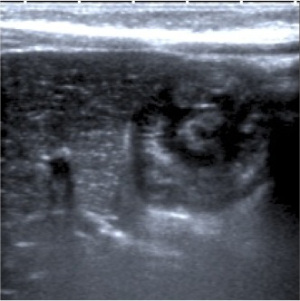

- En la radiografía (no esta indica su realización) se aprecia ausencia de aire con efecto masa y distensión de asas en el abdomen izquierdo. Se realiza Ecografía como prueba de elección para confirmar el sospecha clínica.

El diagnóstico actual de la se realiza mediante TC abdominal:

- El hallazgo patognomónico es el signo de la escarapela o diana identificable en la TC o ecografía.

- Podemos ver la imagen de “Intestino dentro de intestino” gracias a las reconstrucciones multiplanares.